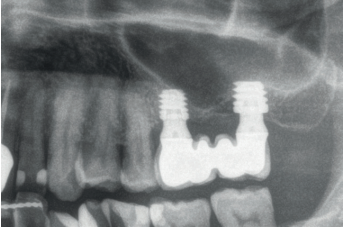

Todos los pacientes fueron tratados por un mismo cirujano, para la realización de la inserción de los implantes y la técnica de elevación transcrestal. Antes de la inserción de los implantes se utilizó una premedicación antibiótica consistente en amoxicilina 2gr vía oral una hora antes de la intervención y paracetamol 1 gramo vía oral (como analgésico). Posteriormente los pacientes prosiguieron con un tratamiento de amoxicilina 500-750 mg vía oral cada 8 horas (según peso) durante 5 días. Todos los pacientes fueron estudiados antes de la inserción de los implantes mediante modelos diagnósticos, exploración intraoral y realización de una tomografía computerizada de haz cónico (CBCT), analizado posteriormente mediante un software específico (BTI-Scan III). La cirugía se lleva a cabo mediante la técnica de fresado biológico descrita por nuestro grupo de estudio previamente, a bajas revoluciones, sin irrigación10, hasta ser finalmente completada mediante la elevación transcrestal con las fresas de corte frontal que se emplean también a bajas revoluciones. Una vez la membrana es accesible mediante la perforación crestal se despega mediante una ligera presión y se inserta el implante con el motor quirúrgico fijado a 25 Ncm y 25 rpm finalizando la inserción del implante con la llave dinamométrica. Todo el hueso recogido con las fresas se conserva en PRGF-Endoret fracción 2 sin activar, para posteriormente ser utilizado como injerto óseo particulado en la elevación, sin otros materiales accesorios9,12. Una vez finalizada la cirugía se realiza una radiografía periapical con paralelizador que será la que se utilice como punto de partida. Los pacientes acuden posteriormente para la realización de radiografías periapicales de control, tomadas con la misma técnica y sobre estas radiografías se realizan las mediciones necesarias para comprobar la estabilidad y pérdida ósea crestal de los implantes. La medición de la pérdida ósea marginal se realizó en la última radiografía periapical realizada con posicionador de seguimiento.

Una vez obtenida la radiografía en formato digital es calibrada mediante un software específico (Digora for Windows, SOREDEX Digital Imaging systems) a través de una longitud conocida en la radiografía como es el implante dental. Una vez se introduce la medida de calibración, el programa informático realiza un cálculo basado en esta medida para eliminar la magnificación, pudiendo realizar mediciones lineales exentas de este error. La pérdida ósea crestal fue medida en dos puntos: mesial y distal de cada implante. El implante fue la unidad de análisis para la estadística descriptiva en cuanto a la localización, dimensiones del implante, y mediciones radiográficas. La variable principal fue la supervivencia del implante y como variables secundarias se registraron la pérdida ósea mesial y distal. Fue realizado el test de Shapiro-Wilk sobre los datos obtenidos para verificar la distribución normal de la muestra. Las variables cualitativas se describieron mediante un análisis de frecuencias y las variables cuantitativas se describieron mediante la media y la desviación estándar. La supervivencia de los implantes se calculó mediante el método de Kaplan-Meier. Los datos fueron analizados con SPSS v15.0 para windows (SPSS Inc., Chicago, IL, USA).

En la Figura 2 se muestran los diámetros y longitudes de los implantes incluidos en el estudio en función de los milímetros de cresta ósea residual en altura. La densitometría media de la zona de inserción del implante del grupo fue de 293,33 HU (+/- 144,99). El torque medio de los implantes estudiados fue de 27,33 Ncm (+/- 16,99). Todos los implantes se cargaron en dos fases quirúrgicas y en todos se llevó a cabo una elevación de seno transcrestal con injerto óseo autólogo particulado obtenido del fresado, embebido en PRGF-Endoret como marterial de injerto. En ninguno de los casos se registraron complicaciones relativas a la cirugía. Los implantes presentaron un seguimiento medio de 13,33 meses tras la carga (+/- 3,09), no encontrándose complicaciones ni fracasos durante este tiempo de seguimiento, por lo que la supervivencia fue del 100%. Todos los implantes fueron rehabilitados mediante prótesis múltiple atornillada mediante elemento intermedio (transepitelial múltiple, Multi-im®), encontrándose dos de los implantes ferulizados a otros de la misma longitud (4,5 mm) y el resto a longitudes mayores. La ratio corona-implante medio para el grupo de estudio fue de 2,43 mm (+/-0,45). La pérdida ósea mesial final media de todos los implantes fue de 0,42 mm (+/- 0,51) y la pérdida ósea distal final media de 0,16 mm (+/-0,34). En las Figuras 3 –13 se muestra uno de los casos incluidos en el estudio.